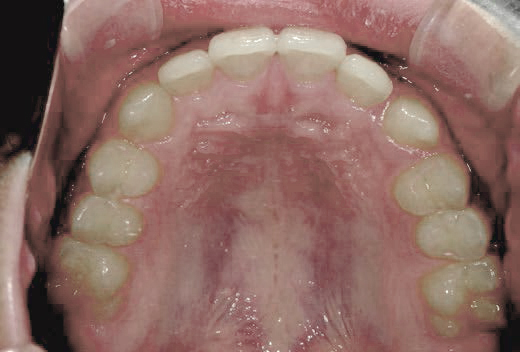

出っ歯

「本当に永久歯を抜かずに治るの?」半信半疑で相談に来られました

Mさん (矯正開始時:8歳)

Before

After

これから生えてくる永久歯のスペースがなく、歯が並ぶ余地がほとんどありませんでした。

さらに、上からあごの骨を見たところ、中央がくびれた“ひょうたん型”に変形しており、あごの成長にも偏りが見られました。

診断の結果、前歯の中心も少し左にずれており、特に犬歯が生えるスペースが足りない状態でした。

飲み込むときに下くちびるに力が入り、顔の左側にゆがみが出ている様子も確認できました。

治療を終えて

犬歯が歯ぐきの中に埋まっていたため、透明のマウスピース型装置で生えるスペースを作り正しい位置に導きました。もちろん抜歯せずに歯並びを整えることができました。お口の中がとても小さく、型どりの際にオエッとなる反応が強く、当時は装置を作るのが大変でした。しかし現在では3Dスキャナーと3Dプリンターを活用しスムーズに治療できます。

主訴・治療内容 「あごが小さいから、歯がきれいに並ばない」と他院で言われ永久歯を抜く矯正をすすめられていました。

本当に非抜歯で治療できるのか心配されていましたが、治療方法を丁寧にご説明し、お任せいただきました。

治療期間 5年

費用 550,000円(税込)